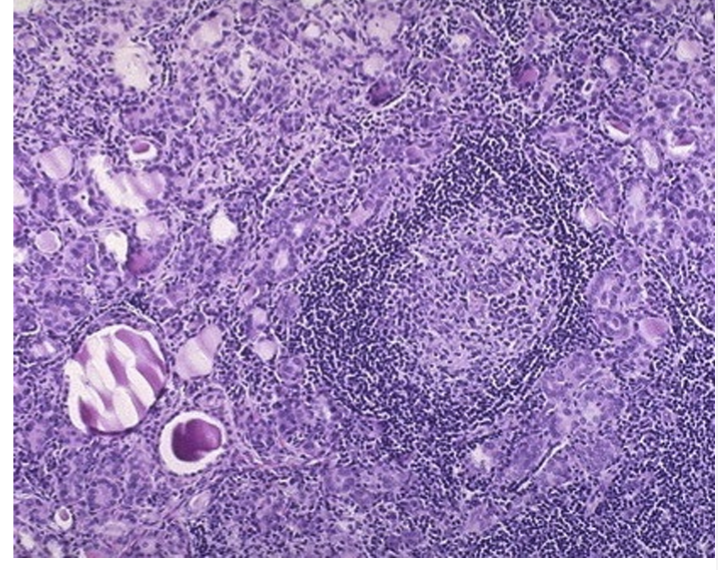

What disease is this

Hashimoto’s disease